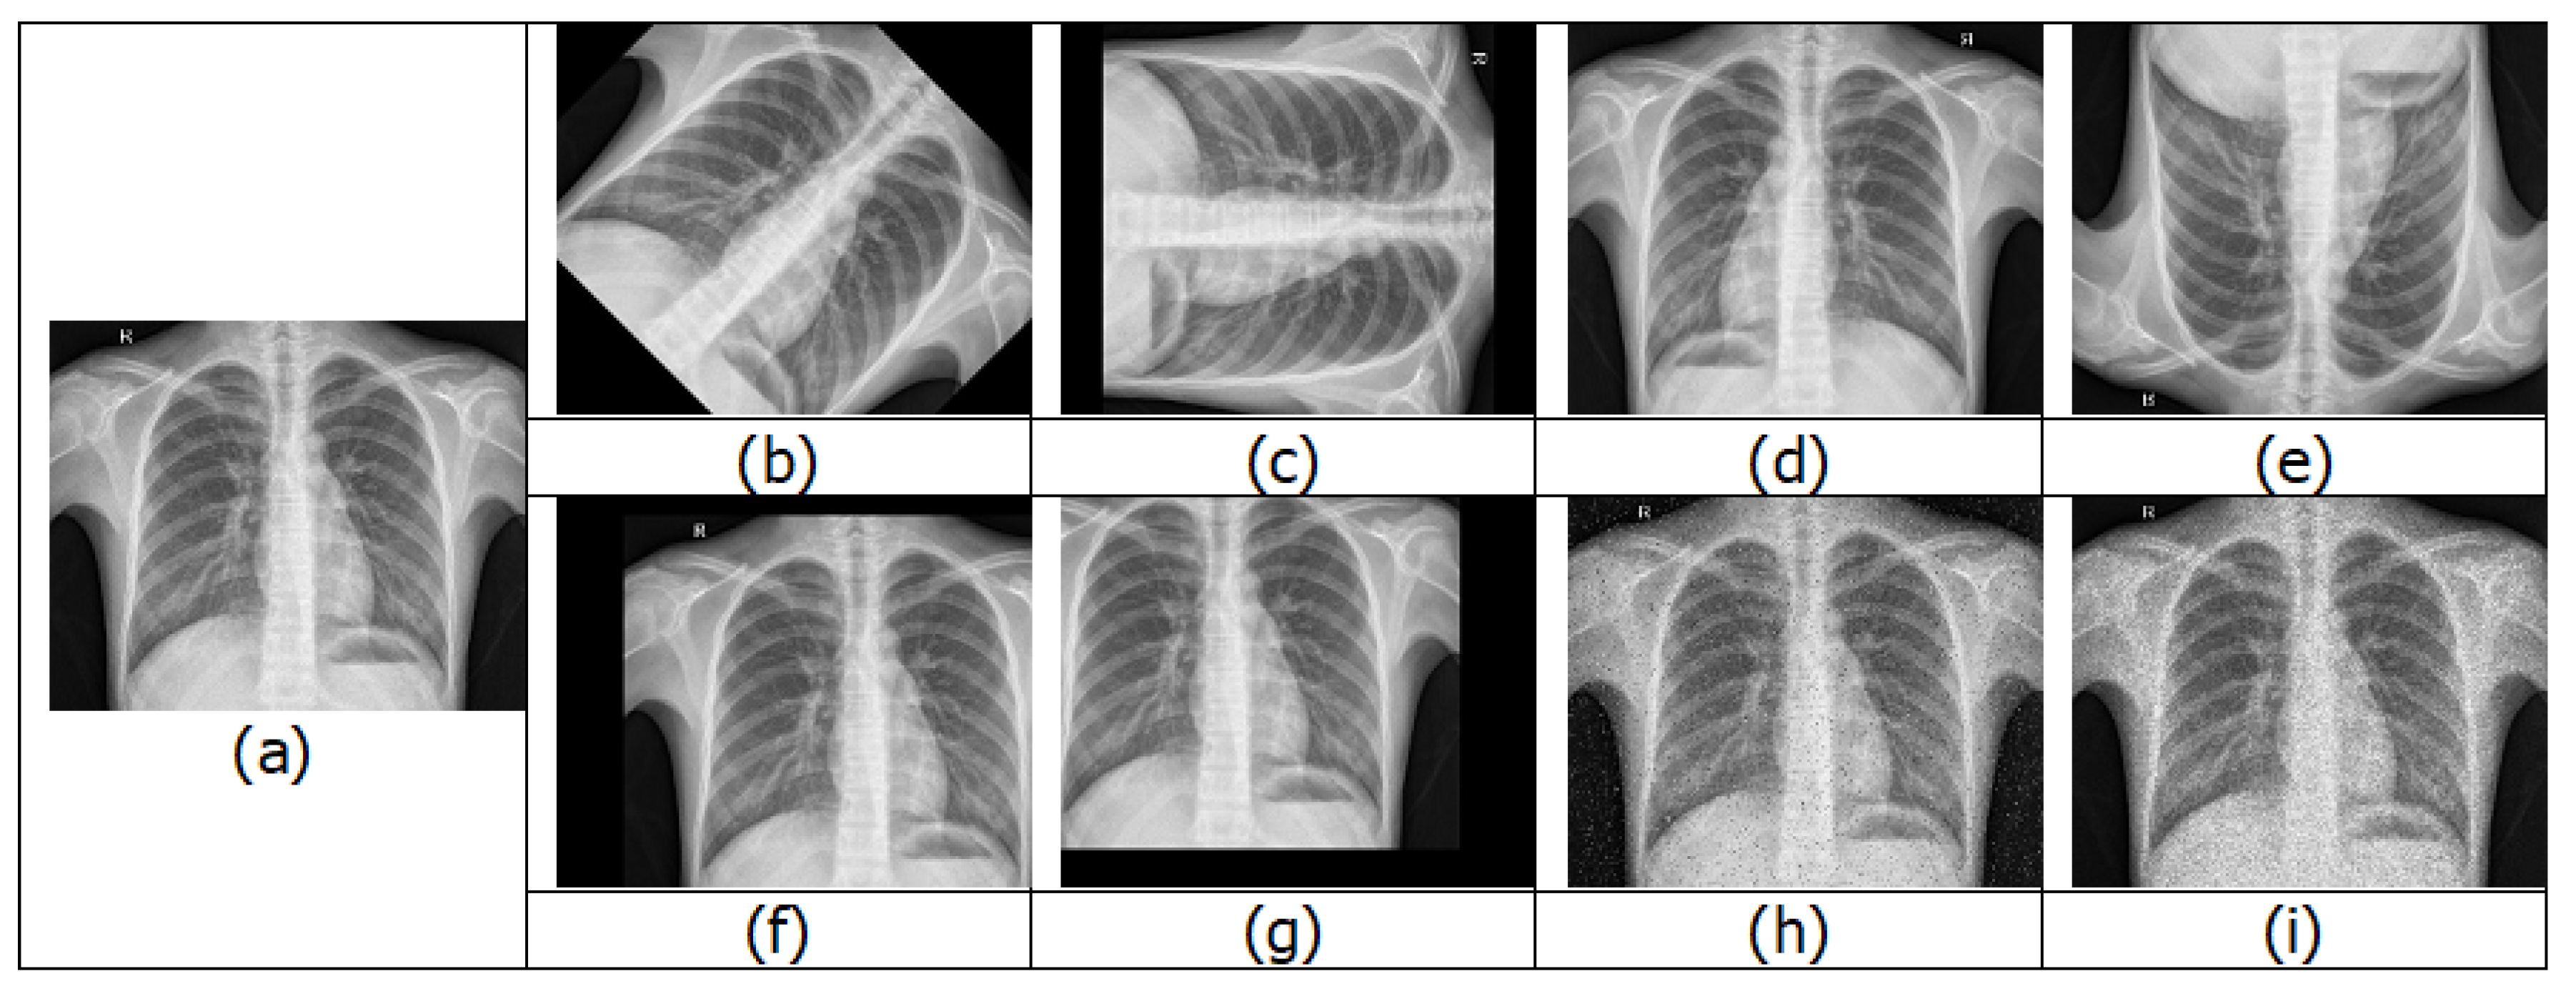

4.1.1. Chest X-rays